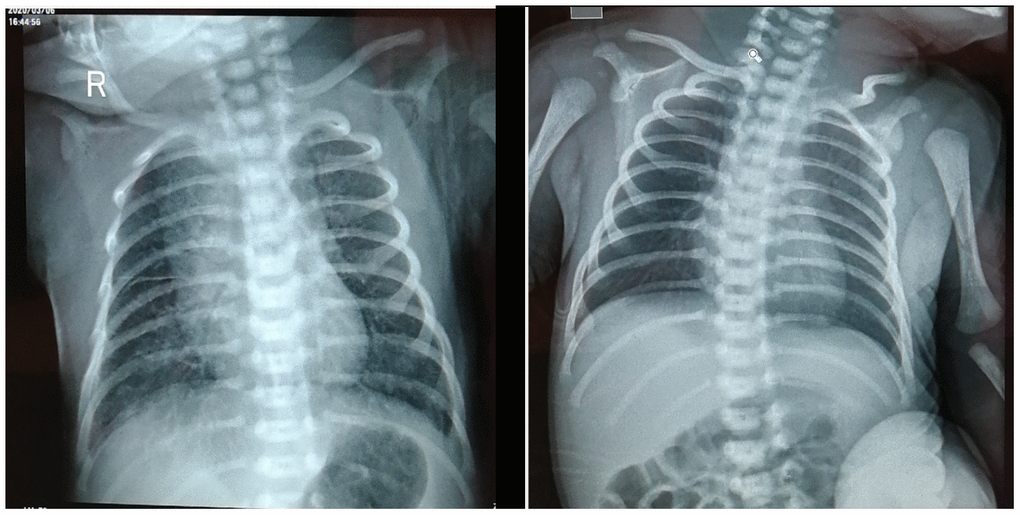

Laboratory reports of this infant were negative, including toxoplasma, herpes simplex virus 1/2, cytomegalovirus (CMV), and rubella virus. Neutrophils percentage (69.5%, normal: 31% ~ 52%), basophilic cells percentage (0.70%, normal: 0% ~ 0.6%), neutrophils total (13.45%, normal: 3.9% ~ 9.4%) were all increased. Liver dysfunction (AST 92U/L, normal: ≤41 U/L), creatine kinase (189U/L, normal: 30 ~ 170 U/L), creatine kinase isoenzyme MB (60U/L, normal: 0 ~ 24U/L) levels increased. Procalcitonin increased (0.880ng/ml, normal: ≤0.05ng/ml). IL-6 (49.00pg/ml, normal: 0 ~ 20.9pg/ml) and IL-10 (6.28pg/ml, normal: 0 ~ 5.9pg/ml) increased. Renal function and electrolytes were normal. Figure 1A Chest X-ray showed enhanced lung veins, reticular and patchy shadows, and no abnormalities in heart and palate (image). She was closely monitored in isolation, treated with a nourishing cardiac muscle and a spray of interferon. Intravenous injection of penicillin G (15wu q.d, intravenous bolus) and vitamin K1 (1mg q.d, intravenously) were used as antibiotics and to prevent coagulation disorders.

Figure 1. Chest X-ray of neonate on March 6th, 2020 (A) and March 12th, 2020 (B).

From March 7 to March 12, 2020 the newborn's vital signs were stable, the blood oxygen saturation maintaining above 90%, and there was no apnea or vomit. On March 9, the nucleic acid test of neonatal COVID-19 pharyngeal swab was negative, however, and serum COVID-19 IgM and IgG antibodies were normal and strong positive, respectively. The blood routine, liver function, calcitonin, and creatine kinase levels all returned to normal. Chest X-ray of neonate showed a few flaky shadow, with no abnormality in heart and palate. Compared with the chest X-ray on March 6, the Chest X-ray Figure 1B of March 12 revealed that most of the lung lesions were absorbed. She did not receive any special treatment since March 12. On March 17, laboratory tests and chest radiographs were normal, the nucleic acid test of neonatal COVID-19 pharyngeal swab and serum IgM were both negative. The newborn was discharged from hospital on March 18, 2020.